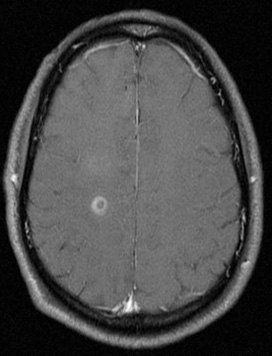

Séries de imagens de ressonância nuclear magnética (RNM) do cérebro de um paciente com encefalomielite disseminada aguda: imagem de pós-contraste com gadolínio em T1 mostra o realce em anel ao redor de uma lesão na região do centro semioval e realce fraco difuso logo acima dessa área

Do acervo pessoal de Catalina C. Ionita, MD; usado com permissão

Veja esta imagem em contexto nas seguintes seções: